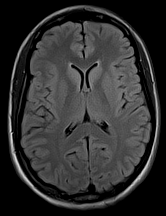

3.2.2 Example 1: Scan acceleration

The used data is obtained from the publicly available fastMRI brain dataset (citep \@BBN(Zbontar et al., 2019)), which consists in total of 640564056405 T1, T2 and FLAIR 3D k-space volumes. The fastMRI challenge series provided MRI datasets to foster the development of accelerated reconstruction algorithms. The series consists of a knee MRI dataset and challenge in 2019 (citep \@BBN(Knoll et al., 2020)), of a brain dataset and challenge in 2020 (citep \@BBN(Muckley et al., 2021b)), and of a prostate dataset in 2023 (citep \@BBN(Tibrewala et al., 2023)). The winners of the challenges were selected by the comparison of the provided reference images, created by the rSOS of the fully sampled data, to the image outputs of the proposed method via the SSIM and the highest ranked results were submitted to receive experts’ opinion.

We show here images obtained from two machine learning reconstruction algorithms that took part in the fastMRI multi-coil brain dataset challenge in 2020, namely the end-to-end variational network E2E-VarNet (citep \@BBN(Sriram et al., 2020)) and XPDNet (citep \@BBN(Ramzi et al., 2021)). XPDNet was among the top three submissions of the challenge and both algorithms perform very well on the corresponding public leaderboard (citep \@BBN(Facebook AI, )), that allows comparison of algorithms submitted after the challenge deadline. The authors of the XPDNet Algorithm provided two distinct models for the acceleration factors, we employ the neural network provided for acceleration factor 4.

The reconstructions in Figure 5 were obtained by the application of E2E-VarNet, Figure 5 (b)(c)(e)(f), and XPDNet, Figure 5 (a)(d), to accelerated data with random masks (acceleration factor between 1 to 5) in the frequency domain.

Refer to caption

(a) (27.8, 0.78, 0.14)

(b) (29.6, 0.85, 0.14)

(c) (32.3, 0.92, 0.04)

(d) (29.5, 0.84, 0.12)

(e) (29.6, 0.86, 0.12)

(f) (33.0, 0.94, 0.04)

Figure 5: Reconstruction outputs of accelerated FLAIR MRI data from the algorithms Xpdnet(a)(d) and E2varnet (b)(c)(e)(f). The bottom images (d)-(f) are judged by PSNR/SSIM/LPIPS as better reconstructions than the respective image above them (a)-(c), although visually they clearly have worse quality.

FR-IQA mismatch

We can see in Figure 5 that the visual quality of the obtained images does not correspond to the numbers provided by PSNR/SSIM/LPIPS. This is not surprising as some challenges with SSIM as a performance metric have already been discussed in the official results paper of the challenge (citep \@BBN(Muckley et al., 2021a)) and small artefacts/wrong lesions have been shown. Here, we complement with examples where the visual results clearly ask for a different judgement even in a non local manner. In particular, the bottom images in Figure 5 show stronger artefacts and loss of information in comparison to the images on top. In addition, the degraded images (e) (f) do hold quite higher numbers in comparison to (a) which is nearly noise-free.